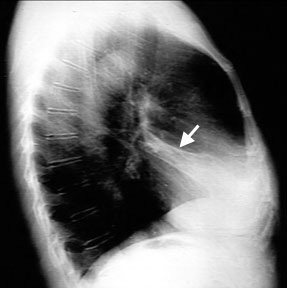

RML atelectasis

Vague density in the right lower lung field. It can easily be missed in PA view.

Minor loss of right heart silhouette.

Triangular density in the lateral chest with narrow end towards hilum.

Loss of lung volume:

• Movement of transverse fissure (White arrow) towards the oblique fissure.

• Volume of RML is less than 5% of total lung volume and as such you will not see elevation of right hilum in PA view chest.

This is a case of RML resorptive atelectasis due to obstruction of the RML.